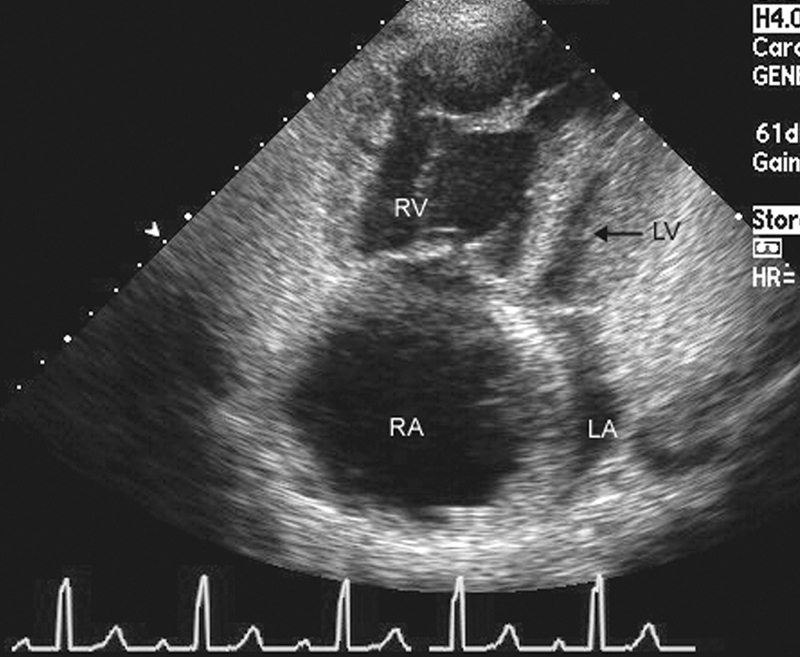

فحوصات تشخيصية لبعض امراض القلب والشرايين التاجية